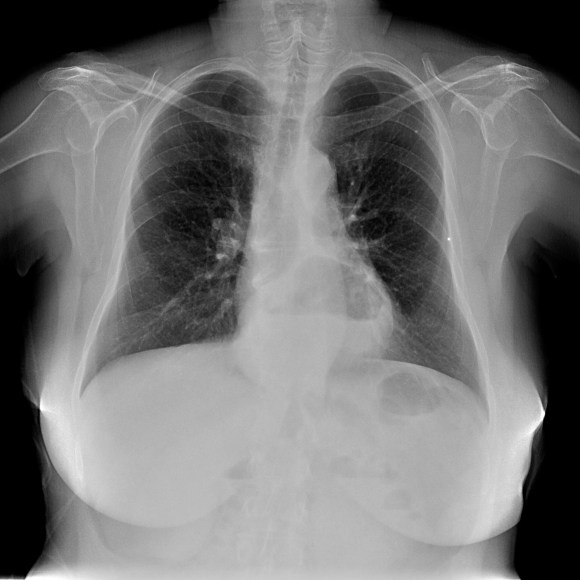

Empecemos, ¿qué ves?

- Comprobar que la placa está bien centrada e inspirada (6 arcos costales anteriores ó 9 posteriores).

- Abdomen y Diafragma

- Partes blandas y estructura ósea.

- Mediastino con silueta cardiaca.

- Parénquimas pulmonares (por separado)

- Comparar un pulmón con otro.

Seguir esta sistemática, dejando el pulmón para el final no nos olvidaremos de lo más importante.

Regla: Acaso Tiene Mucha Patología Pulmonar (Abdomen, Tejidos blandos y hueso, Mediastino, Pulmón por separado, Pulmón bilateral)

Nota: ¡¡¡No olvidar la placa lateral!!! La regla a seguir es la misma. Leer abdomen y diafragma, examinar parte posterior, tejidos blandos y subir por la columna; tráquea y descender por mediastino. Finalmente pulmones.

Solución: Es un estudio Normal. Silueta cardiomediastínica y parénquimas pulmonares sin alteraciones significativas.